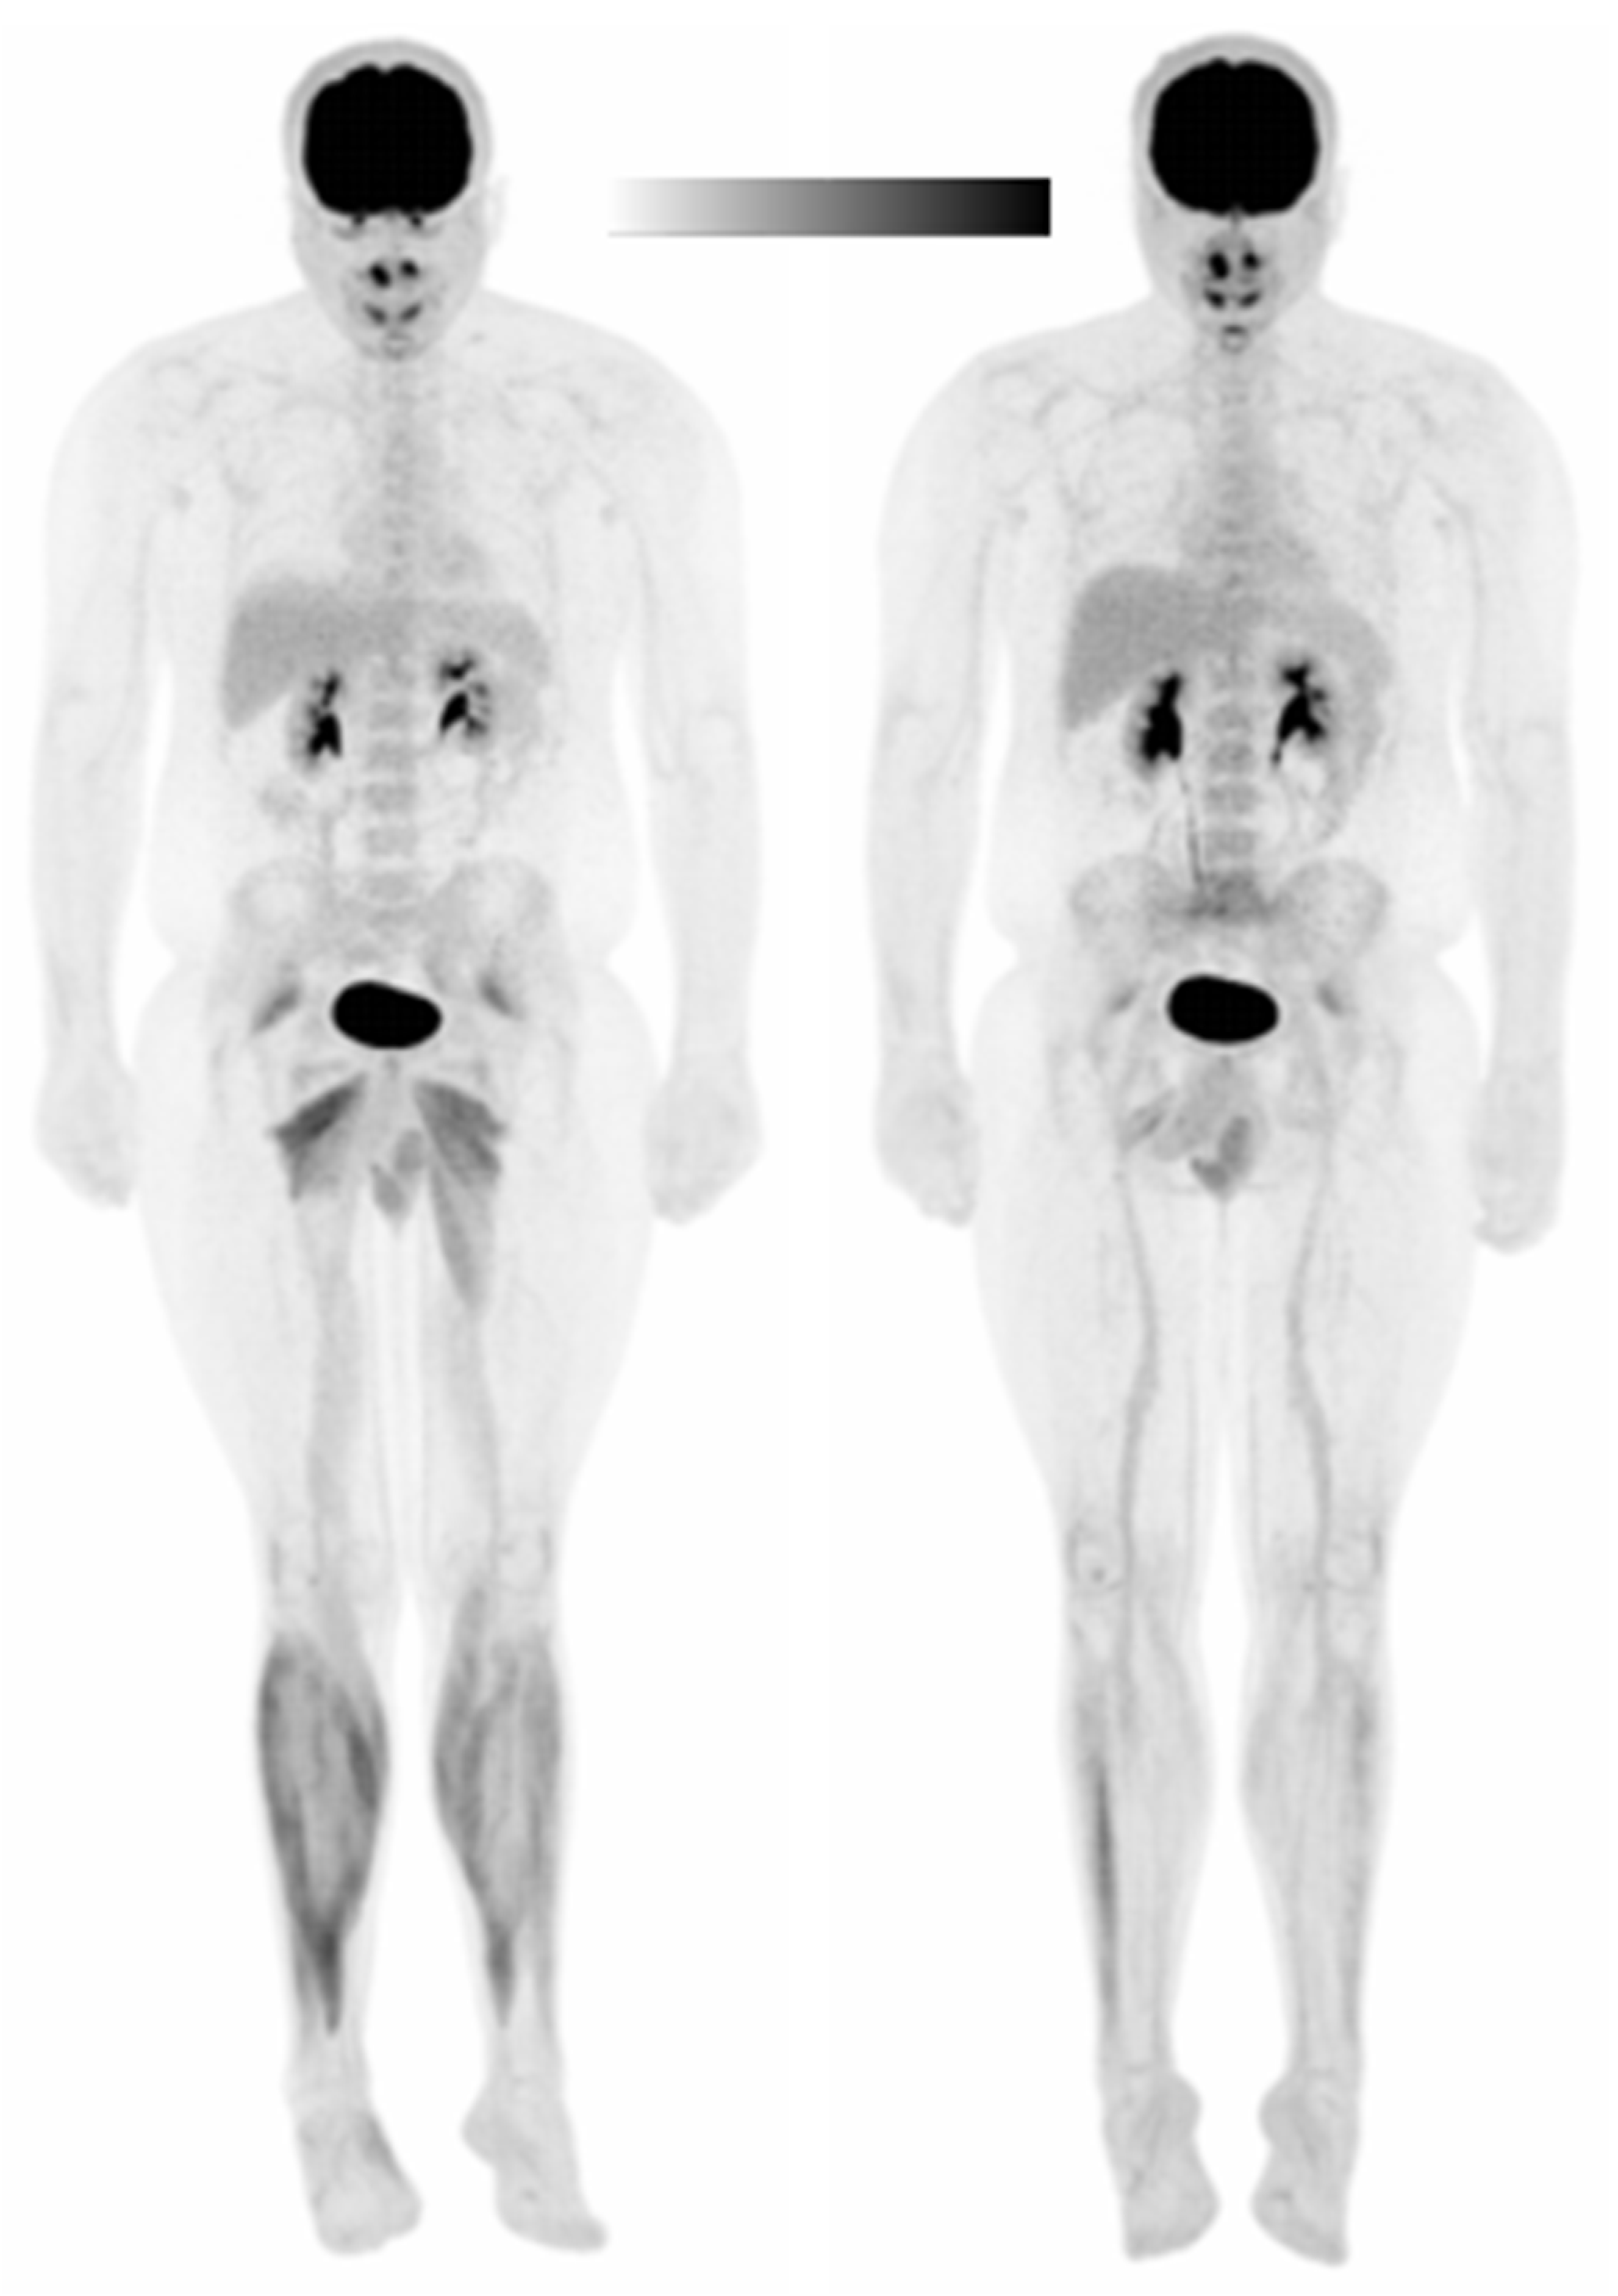

2.5. PET/CT Imaging